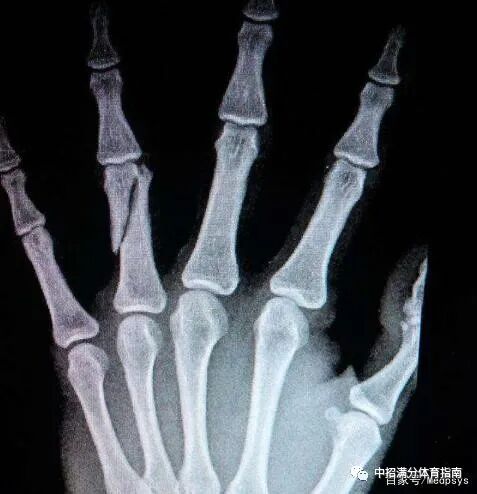

四、指(趾)骨骨折

指(趾)骨分为近节、中节(踊趾无中节)及远节趾骨。趾(指)骨是除踝关节以外活动度最大的部位,又由于位于足的前端,因此也是最容易受伤的部位。开放骨折多见。踢撞硬物致伤多发生横形或抖形骨折。

处理:将患者受伤部位抬高,略高于心脏部位,利于血液回流,减轻局部组织肿胀,简单固定包扎后立即送医,切记不可旋转受伤部位。